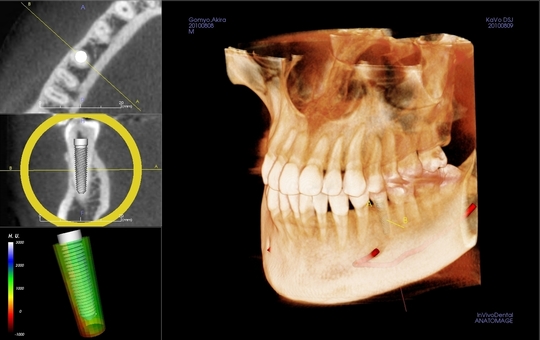

Ctを使った治療 平沢歯科 秦野市